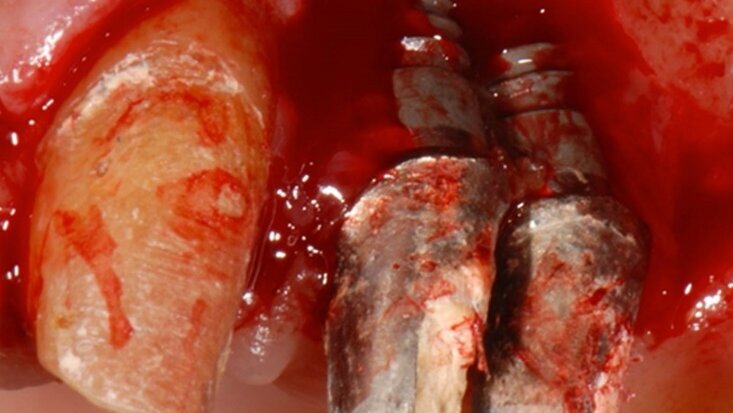

La paziente, di 64 anni, sana e non fumatrice, veniva riferita per un ascesso in corrispondenza di un ponte cementato su pilastro naturale e su impianti, da 2.3 a 2.5 con un elemento in estensione (Fig. 1). L’esame clinico e radiografico mostrava una perimplantite non trattabile a carico di entrambi gli impianti, una grave atrofia ossea e un mucocele asintomatico nel seno omolaterale. Rimossi gli impianti (Fig. 2), la paziente acconsentiva all’esecuzione di un rialzo di seno e una concomitante rigenerazione ossea verticale, e l’inserimento differito di quattro impianti da caricare possibilmente per via immediata. Non si è prevista l’asportazione del mucocele, essendo questo di modeste dimensioni e asintomatico. In posizione 2.4 lo spessore crestale era di 8,5 mm e la distanza cresta ossea/pavimento cavità nasale di 4,4 mm. In posizione 2.6 l’altezza della cresta ossea residua era inferiore ad 1 mm (Fig. 3).

Fig. 2 - Aspetto dei due impianti alla chirurgia di rimozione implantare; si noti come il riassorbimento osseo giunge al livello apicale degli impianti.